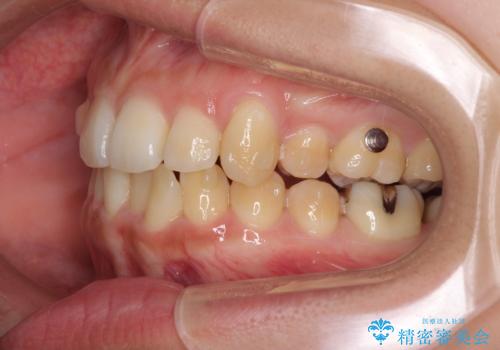

八重歯の抜歯矯正 補助装置を用いたインビザライン矯正

- 下の前歯のデコボコを気にして来院された患者様です。

来院当初、上顎の八重歯は気にしていらっしゃらなかったのですが、矯正治療をするのであれば、しっかりと治した方が良いと説明し、全顎矯正を行うこととしました。

八重歯の移動量が多く、インビザライン単体での治療は困難と判断し、補助装置により八重歯移動後にインビザラインを用いることとしました。